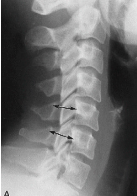

Q what is the name of this measurement? and what is the average + range?

A: Atlantodental Interspace (ADI)

assesses the integrity of the transverse ligament. Average and range for Adults: 1-3 mm. Average and range for Children: 1-5 mm